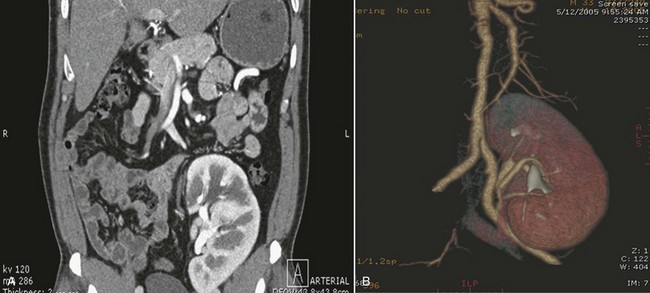

Three-dimensional (3D) volume-rendered CT is a valuable tool in the evaluation of patients undergoing renal surgery (Coll et al, 1999; Derweesh et al, 2003). CT can demonstrate vital information including the anatomy of the renal vasculature, orientation of the kidney, and characteristics of renal tumors, including location, depth of penetration into the kidney, relationship with collecting system, and segmental arterial supply to the tumor (Coll et al, 1999) (Figs. 54-12 to 54-14). CT is also able to characterize other surgically relevant processes, including renal arterial disease, nephrolithiasis, and hydroureteronephrosis (Herts, 2005).

Figure 54–13 CT scan demonstrating two incidentalomas in an elderly man undergoing imaging to rule out appendicitis. A left partial nephrectomy was performed first followed by a right radical nephrectomy in 3 to 4 months.